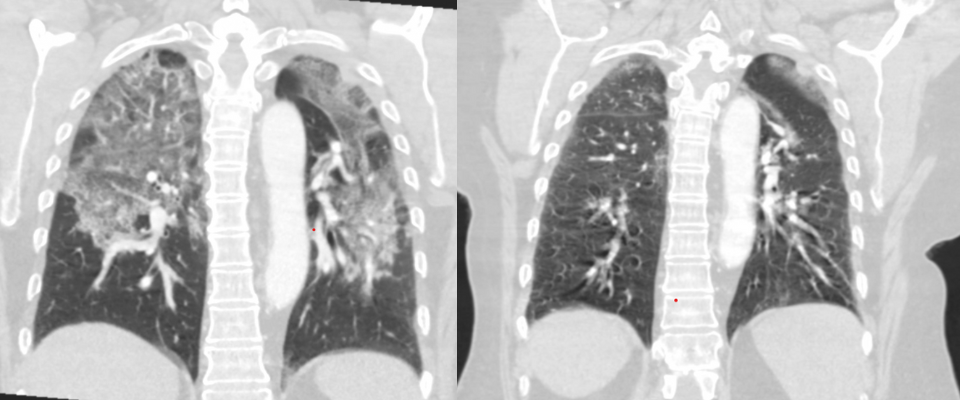

En los últimos años, se ha observado un aumento preocupante en la cantidad de jóvenes menores de 30 años que ingresan a hospitales con problemas respiratorios graves relacionados con el uso de cigarrillos electrónicos o vapeo. Los especialistas han identificado una condición denominada EVALI (Enfermedad Pulmonar Asociada al Uso de Cigarrillos Electrónicos), una inflamación severa de los pulmones provocada por los químicos presentes en los aerosoles que se inhalan al vapear.

Los síntomas de EVALI pueden variar, pero en los casos más severos incluyen dificultad para respirar, tos persistente, dolor en el pecho y acumulación de líquido en los pulmones que, en algunas ocasiones, puede aparecer con rastros de sangre. Algunos pacientes requieren el uso de respiradores artificiales para mantener la oxigenación, mientras que otros desarrollan daño pulmonar permanente, con secuelas similares a las de personas mayores que han fumado durante décadas.

El impacto de EVALI no solo se refleja en los síntomas inmediatos, sino también en las consecuencias duraderas para la salud. Muchos pacientes presentan dificultades para realizar actividades físicas cotidianas, fatiga constante y una mayor susceptibilidad a infecciones respiratorias. Los médicos insisten en que la prevención es la única forma efectiva de proteger los pulmones, ya que una vez que los daños ocurren, la recuperación puede ser parcial o lenta.